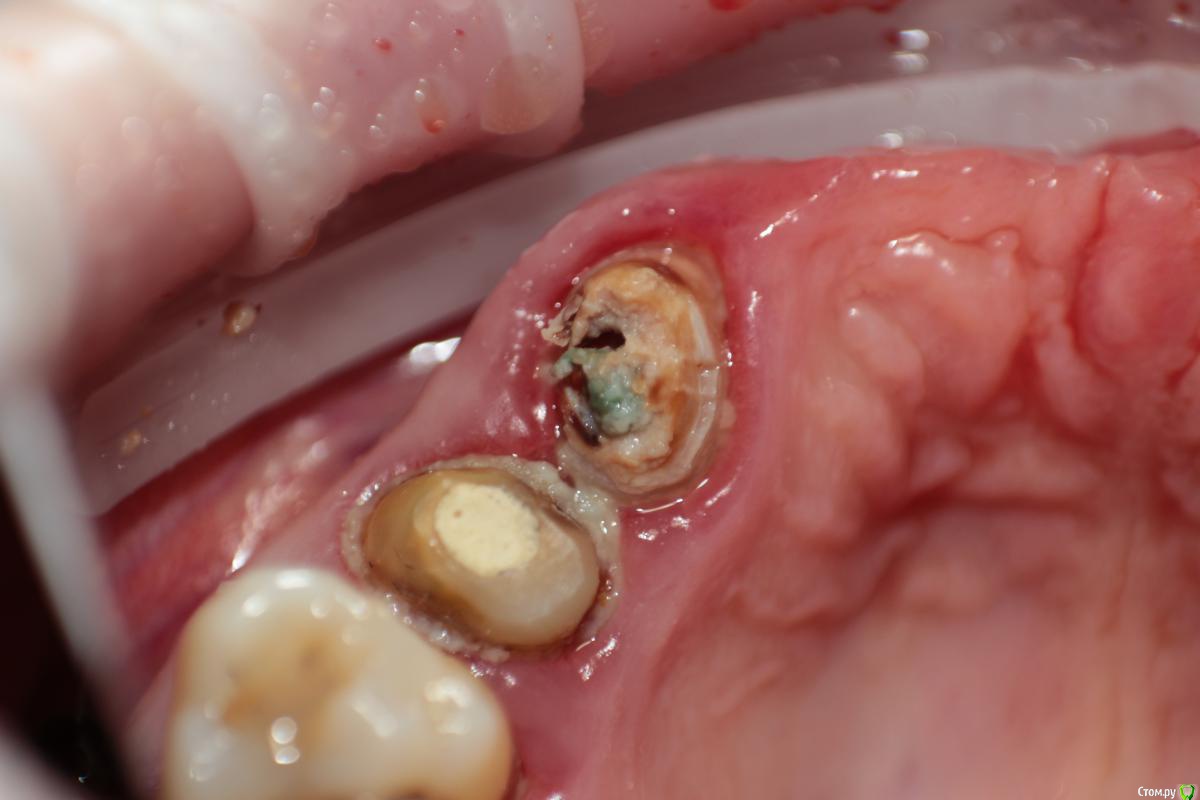

Витторио Орлионе Опубликовано 13 декабря, 2016 Автор Поделиться Опубликовано 13 декабря, 2016 Сегодня мостик сняли и вот что под ним было. А что касается верхних моляров, то 2.8 весь в кариесе, 2.7 уже с 1 степенью подвижности, и выдвинулись они там мм на 3 что в 1м, что во 2м сегменте.пожалуй стоит задуматься о пспп. Ссылка на комментарий

StomV Опубликовано 14 декабря, 2016 Поделиться Опубликовано 14 декабря, 2016 Сегодня мостик сняли и вот что под ним было. А что касается верхних моляров, то 2.8 весь в кариесе, 2.7 уже с 1 степенью подвижности, и выдвинулись они там мм на 3 что в 1м, что во 2м сегменте.пожалуй стоит задуматься о пспп. Вот вопрос о сохранении отпал сам собой. Ссылка на комментарий

Витторио Орлионе Опубликовано 24 декабря, 2016 Автор Поделиться Опубликовано 24 декабря, 2016 на 4.4 зубе штамповка стоит с дыркой на дистальной поверхности, видимо когда-то там был мост, а сейчас через это окно уже деминерализованные внутренности видны, чтоб его сохранить нужно эндо, вкладка и коронка, я склоняюсь к мысли об его удаление, ведь одним искуственным зубом в протезе больше или меньше существенной разницы нет, а вот по стоимости будет как третий пспп. Как бы вы поступили с этим зубом? Ссылка на комментарий